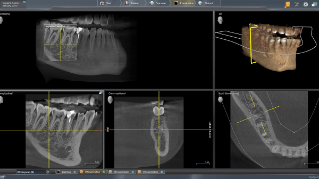

3D示例图

MARS——金属伪影消除软件

金属伪影是3D X射线成像的一大挑战。在三维重建过程中,不透射线的物体会产生阴影和拖尾效应,从而干扰检查结果。MARS自动减少金属伪影,方便诊断。